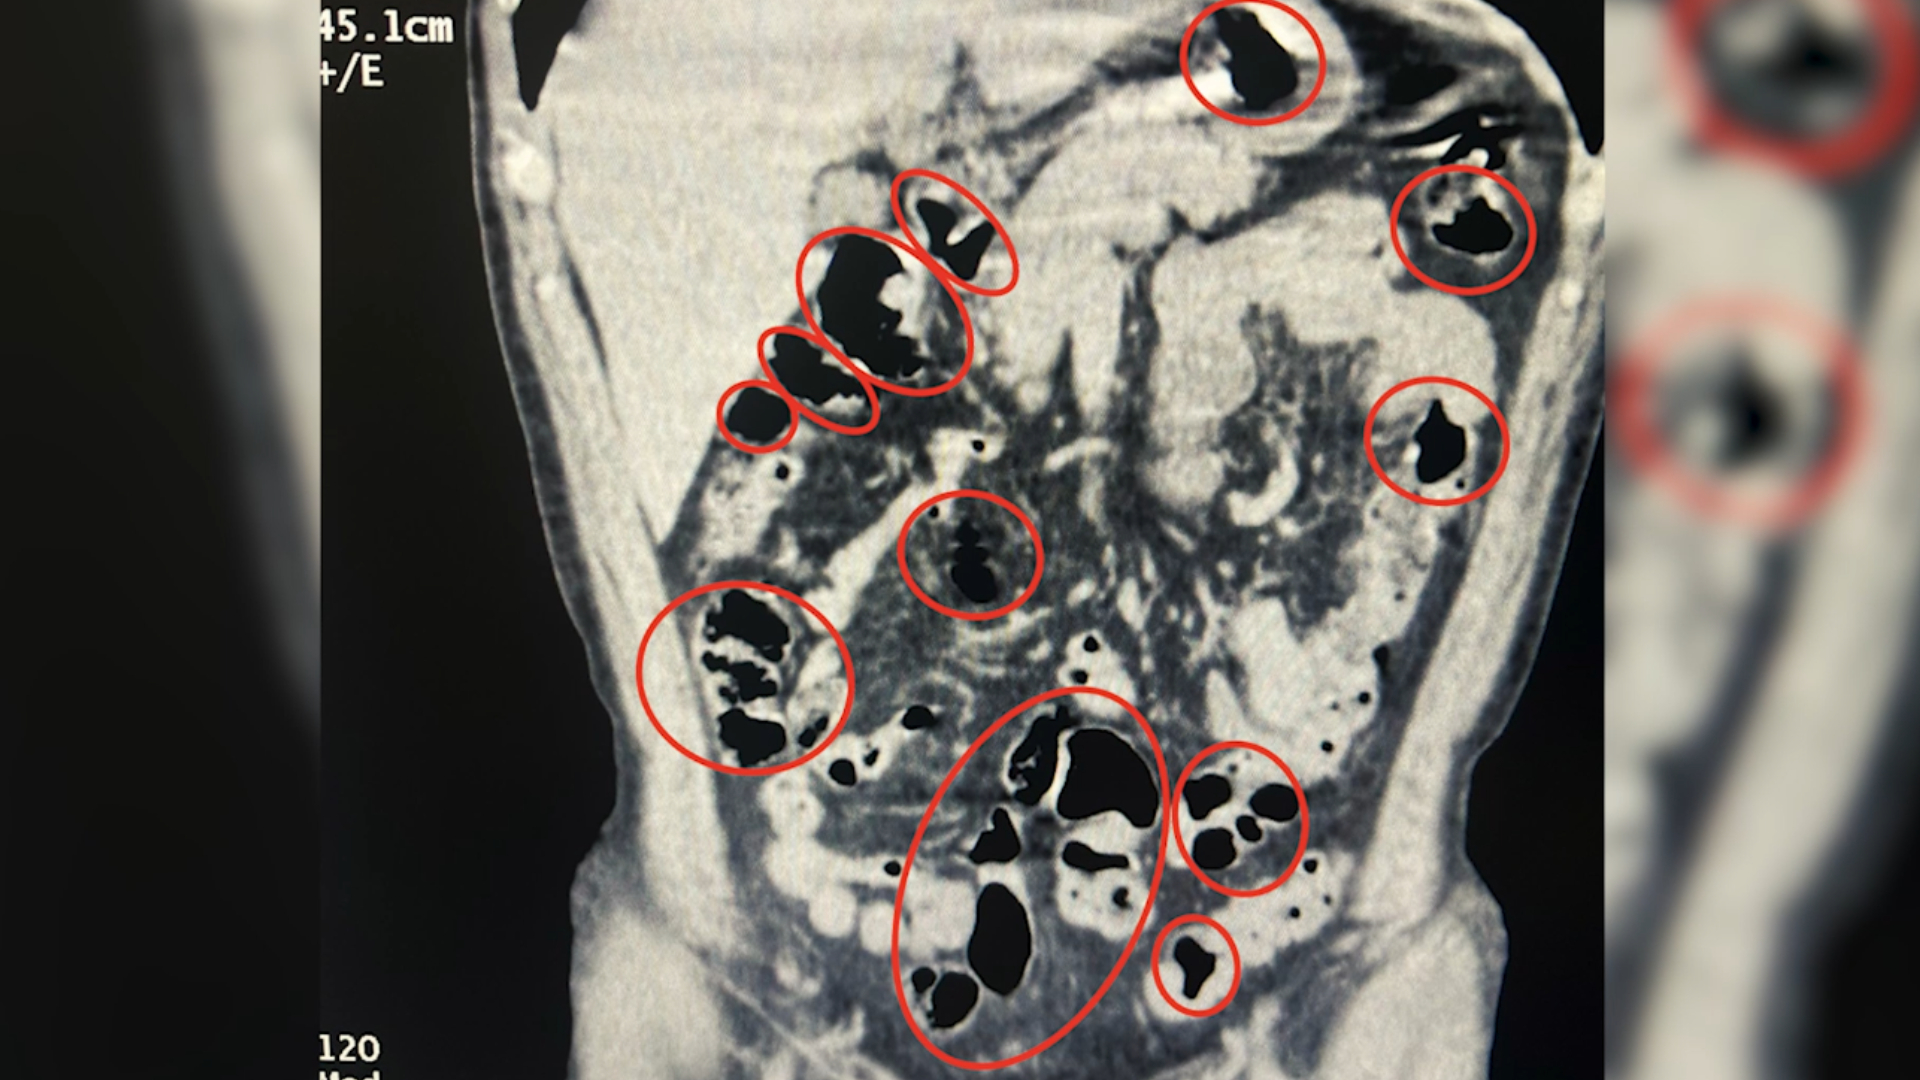

Ayrıca bir otobüste yolcu olarak seyahat eden yabancı uyruklu 2 şahıs gözaltına alındığı kaydedilen açıklamada Tatvan Devlet Hastanesi’nde yapılan röntgen ve tomografi incelemelerinde, şahısların mide ile bağırsaklarında çok sayıda yabancı cisim tespit edildiği ifade edildi. Yapılan tıbbi müdahale ile şahısların yuttuğu 14 kapsül ve üzerlerinden 36 kapsül olmak üzere toplam 50 kapsül 385gram metamfetamin maddesi ele geçirildiği belirtilen açıklamanın devamında her iki olayda da uyuşturucu madde imal ve ticareti suçundan gözaltına alınan 4 şahıstan 3'ü çıkarıldığı adli mercilerce tutuklandığı kaydedildi.